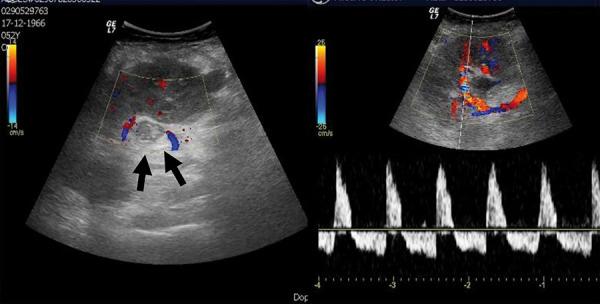

We present a case report of early allograft renal vein thrombosis, preceded by femoral common deep vein thrombosis in a recipient of a third kidney transplant. Despite femoral common deep vein thrombosis treatment with low-molecular-weight heparin and progressive improvement of renal function to a nadir serum creatinine of 0.51 mg/dL, the patient experienced a sudden episode of anuria on postoperative day 5. Doppler ultrasonography strongly suggested the diagnosis of allograft renal vein thrombosis. The patient underwent balloon catheter and aspiration venous thrombectomy, followed by unfractionated heparin perfusion. After 4 days of anuria and multiple blood transfusions, when allograft nephrectomy was contemplated, diuresis suddenly resumed. After 1 year of follow-up, the patient still has a normal renal function.

我们报告一例早期同种异体肾移植肾静脉血栓形成的病例,该患者为第三次肾移植受者,术前存在股总深静脉血栓形成。尽管使用低分子量肝素治疗股总深静脉血栓形成且肾功能逐渐改善至血清肌酐最低点为0.51mg/dL,但患者在术后第5天突然出现无尿。多普勒超声强烈提示同种异体肾移植肾静脉血栓形成的诊断。患者接受了球囊导管和抽吸静脉血栓切除术,随后进行普通肝素灌注。在无尿4天并多次输血后,考虑进行同种异体肾切除时,突然恢复了利尿。随访1年后,患者肾功能仍正常。